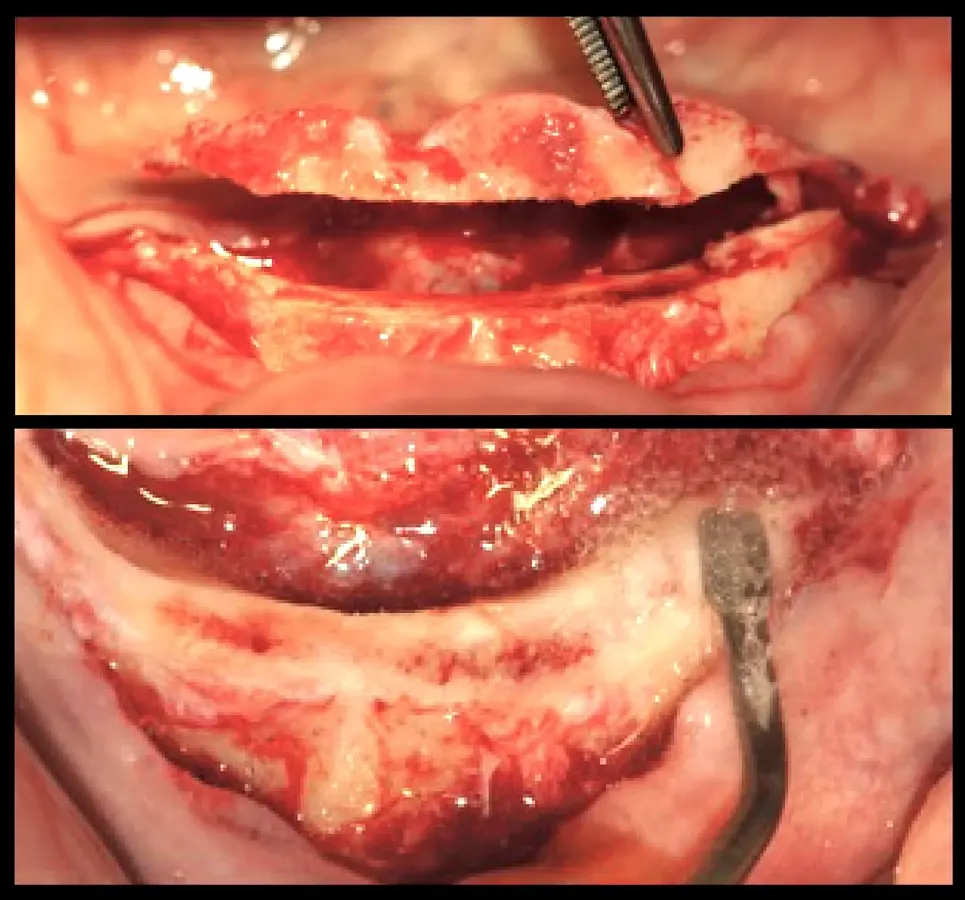

Paciente de ochenta y dos años de edad, de sexo masculino, acudió a la consulta odontológica refiriendo la necesidad de una prótesis inferior y malestar con la prótesis fija superior maxilar. El paciente refirió que le diagnosticaron diabetes mellitus tipo 2 hace 15 años. Refirió también haber tenido carcinoma de próstata y haber recibido radioterapia, hormonoterapia y orquiectomía. La última dosis de radioterapia la había recibido hace 72 meses y fue de 78 Gy en total. El paciente tenía un ASA2 según la clasificación del estado físico de la Sociedad Americana de Anestesiología (ASA)8,9. Asímismo, autorizó la recolección de la información y el uso de fotografías para su publicación con la firma de un consentimiento informado. En la evaluación intraoral, se observó coronas metal cerámicas tipo veneer en las piezas superiores con mala adaptación, acúmulo de placa bacteriana y edentulismo mandibular. Se inició el tratamiento con la motivación e instrucción de higiene oral, se procedió con la eliminación de las bolsas periodontales mediante raspado y alisado radicular. Estabilizada la salud periodontal, se realizó el alargamiento de las coronas clínicas. La gingivectomía se realizó con el electrobisturí (Servotome, Acteon), mientras que para el remodelado óseo se utilizaron los insertos P2LD del piezoeléctrico (Piezomed, W&H) (Figura 2).

Recontorneo gingival

Figura 2. Recontorneo gingival y alargamiento de corona clínica mínimamente invasiva mediante cirugía piezoeléctrica, donde se remodela el hueso sin elevar grandes colgajos (a). Se utilizaron los insertos de piezoeléctrico P2LD de W&H (b).